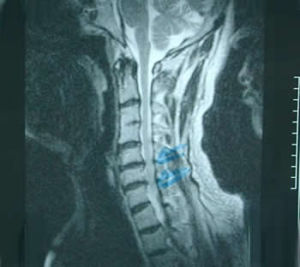

磁共振(MRI)和單光子發射計算機斷層掃描(SPECT):美國科學家研究了36例患者,24例為炎性下背痛,12例為機械壓力所致下背痛的病人.通過標準的X線檢查骶髂關節正常.但套用MRI檢查:發現54%的炎性下背痛和17%的機械原因性下背痛的患者有骶髂關節炎。

用SPECT檢查:發現38%的炎性下背痛存在骶髂關節炎,而機械原因組無此發現.MRI和SPECT同時檢查陽性發現率明顯升高.炎性下背痛者58%和機械性下背痛者17%的患者存在骶髂關節炎。因此研究者認為MRI和SPECT閃爍造影骶髂關節拍片,非常有助於極早期診斷和治療,從這個角度講明顯優於普通X線,但費用昂貴,不提倡作為常規檢查。